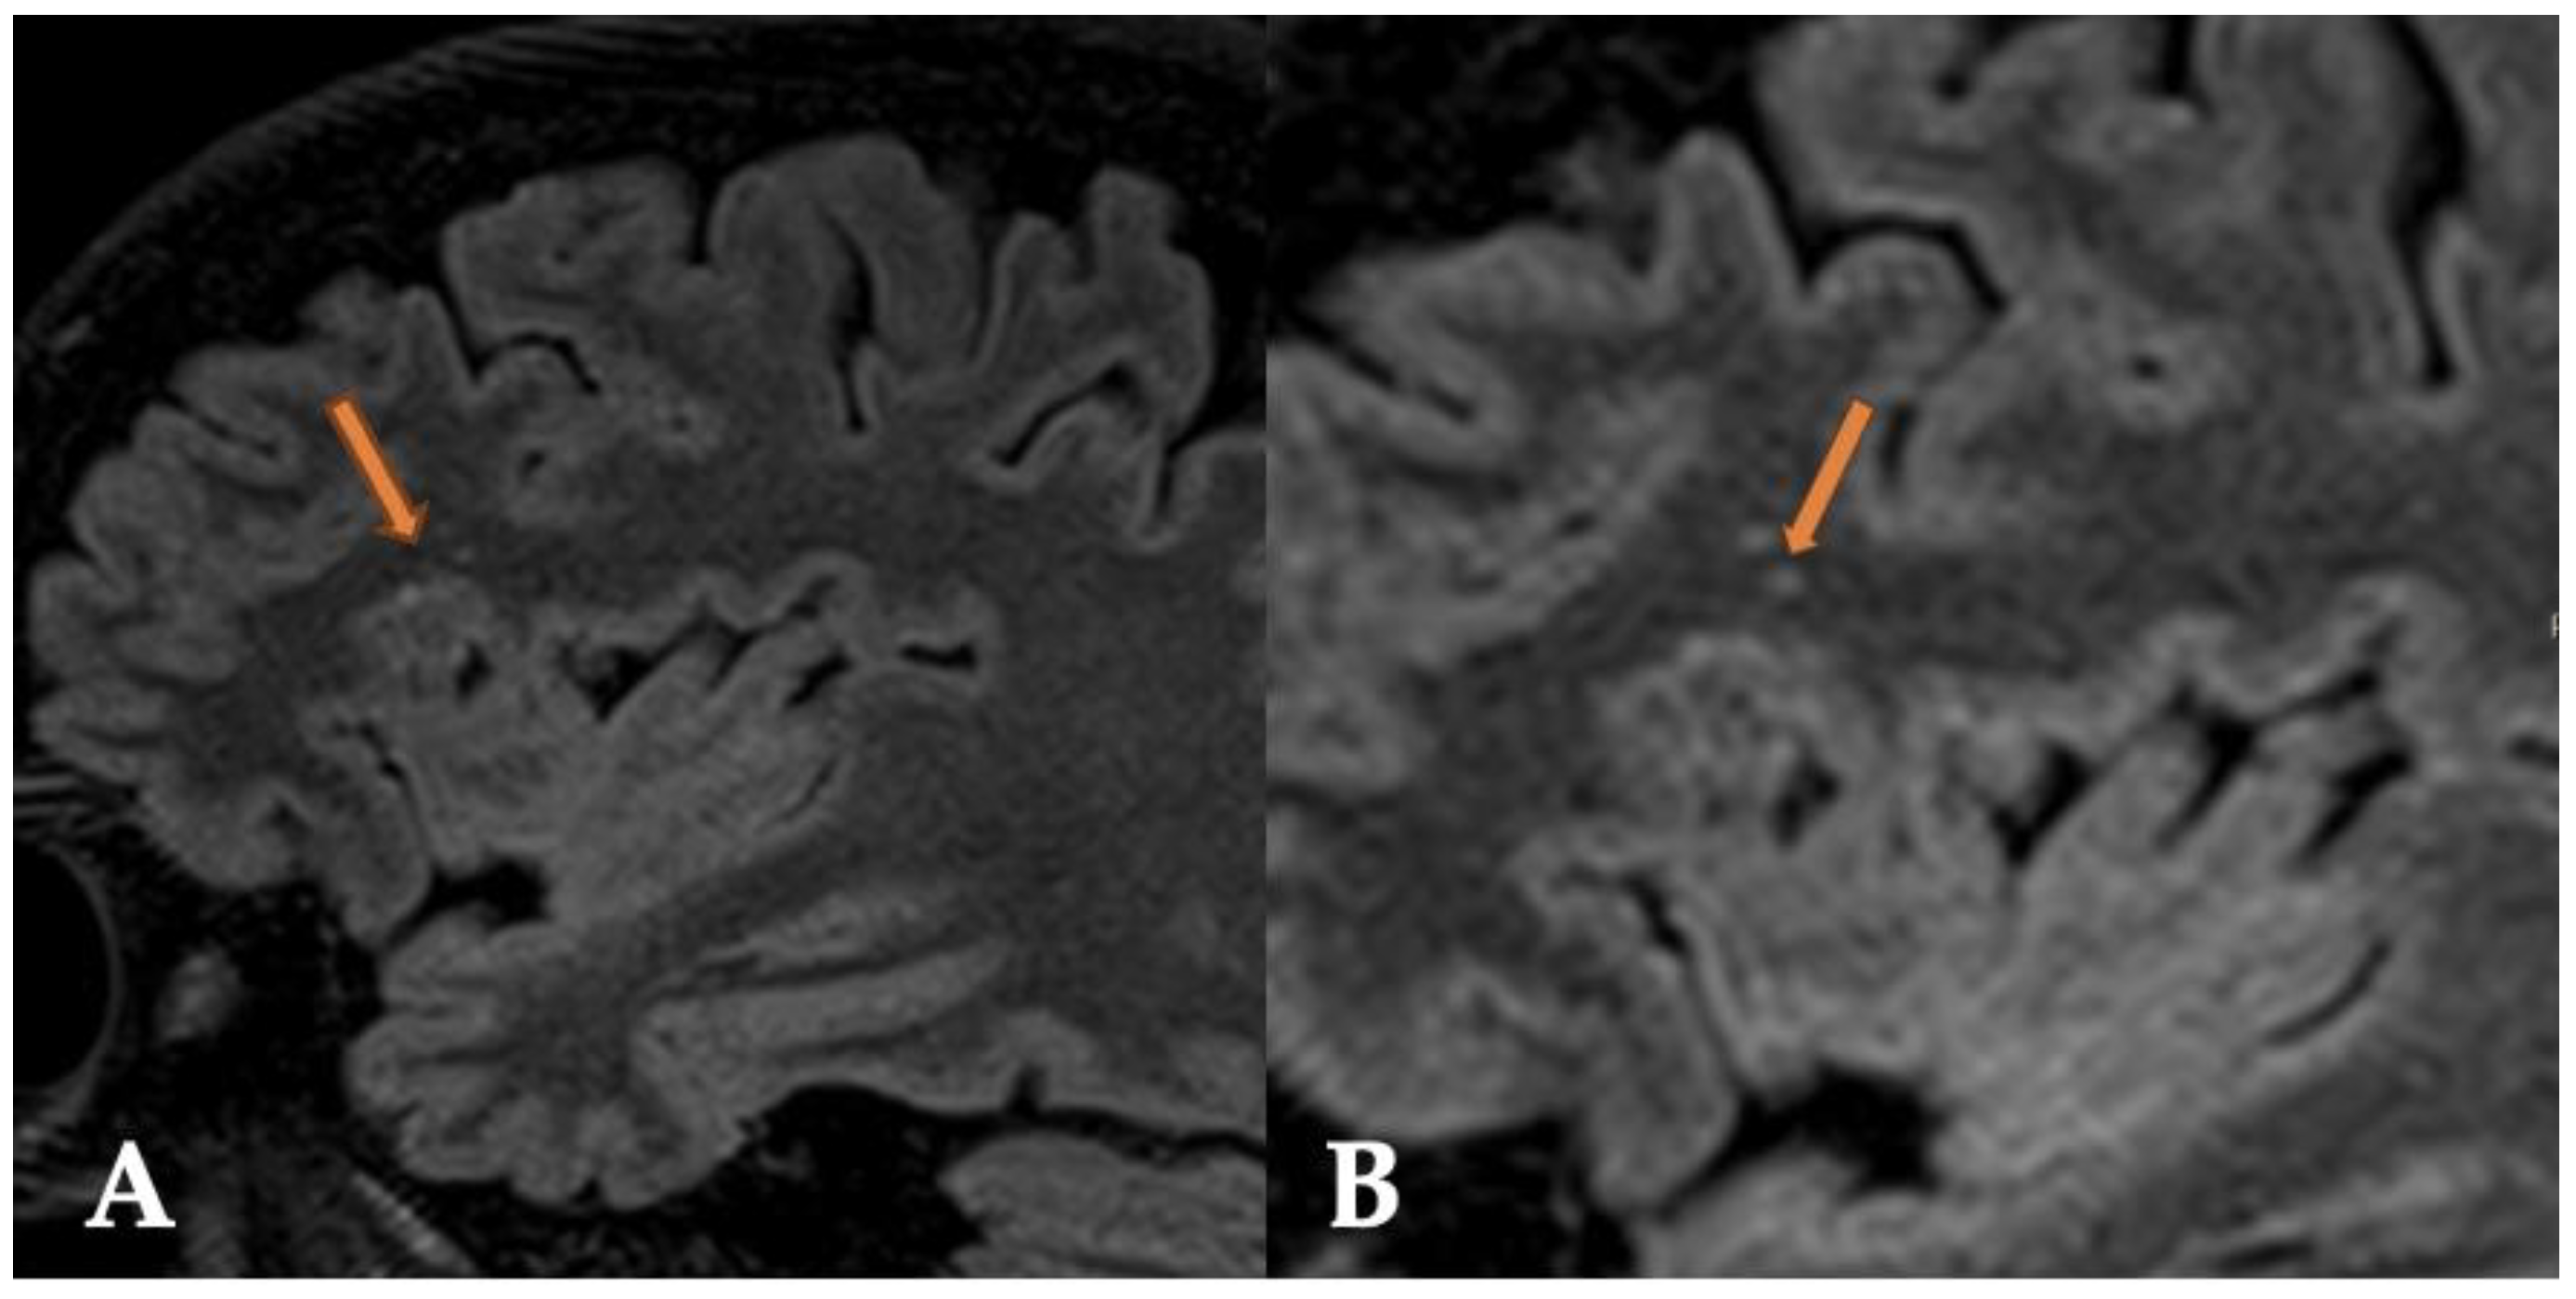

2.1. Case 1

2.2. Case 2